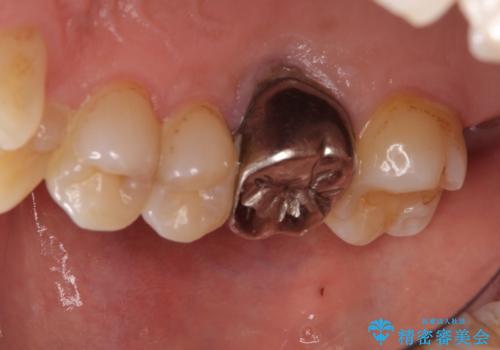

- 2年ほど放置していた左上の仮歯がとれたことをきっかけにご来院された患者様です。

セラミック治療がご希望でしたが、ときどき歯肉が腫れるということで根管治療もご希望されました。

左上の仮歯を2年使用して穴があいて外れたことをきっかけにご来院されました。

レントゲン上からも、歯の中(根管)が汚れている可能性があることをご説明したところ、根管治療からやり直しをすることになりました。